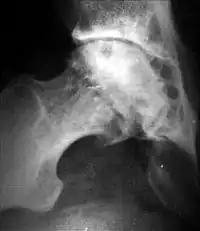

Краевые разрастания (остеофиты) при коксартрозе

Ранним рентгенологическим симптомом являются краевые костные разрастания — остеофиты — следствие активной пролиферации периферических отделов суставного хряща. Они проявляются вначале заострением краёв суставных поверхностей, а затем, нарастая, образуют массивные костные шипы и губы. Краевые остеофиты, как правило, раньше обнаруживаются со стороны суставных впадин.

При остеоартрозе утрачивается амортизационная функция суставных хрящей, предохраняющих костную ткань от механических перегрузок. Как компенсация развивается остеосклероз субхондральной губчатой кости. Особенно он выражен при коксартрозе в крыше вертлужной впадины, распространяясь иногда почти на всё тело подвздошной кости. Однако рано или поздно этот механизм компенсации становится недостаточным. Механические силы, передающиеся непосредственно с одной суставной поверхности на другую, вызывают атрофию от давления их наиболее нагружаемых участков и прежде всего центральных отделов суставных головок. Вследствие этого они уплощаются и одновременно расширяются.

Кистовидная перестройка головки бедра и вертлужной впадины при диспластическом коксартрозе

Результатом поражения суставных хрящей являются очаговые дистрофические и некротические процессы в субхондральной губчатой кости, соответствующие локальным пикам механических напряжений. В результате этих процессов формируются кистовидные образования. Последние наиболее характерны для коксартроза, при котором они часто множественны и достигают больших размеров (эрозивный артроз).